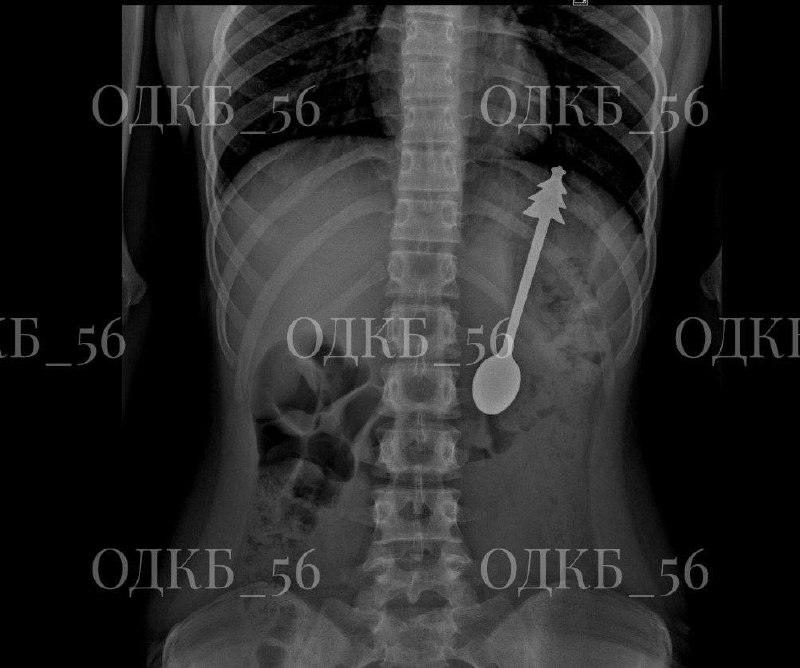

В Оренбурге зафиксирован необычный медицинский случай: ребёнок проглотил ложку длиной 14 сантиметров. Инцидент произошёл в минувшие дни, подробности стали известны благодаря сообщениям местных СМИ.

Пациента оперативно доставили в областную детскую клиническую больницу. После проведения рентгенологического исследования врачи подтвердили наличие инородного предмета в желудке. Медики провели процедуру извлечения ложки, которая прошла без осложнений.